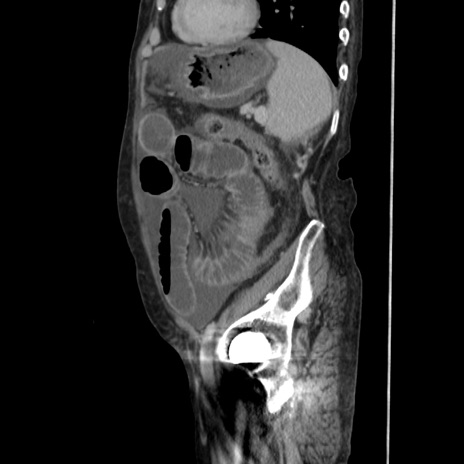

症例31(矢状断像)

【症例】80歳代 女性

【主訴】腹部膨満感

【現病歴】他院にて肝硬変にてフォロー中。1週間前から便秘、腹部膨満感、臍部腫瘤あり受診となる。

【既往歴】肝硬変

【身体所見】腹部膨隆あり、皮膚変化なし、疼痛なし。

【データ】WBC 4600、CRP 0.25